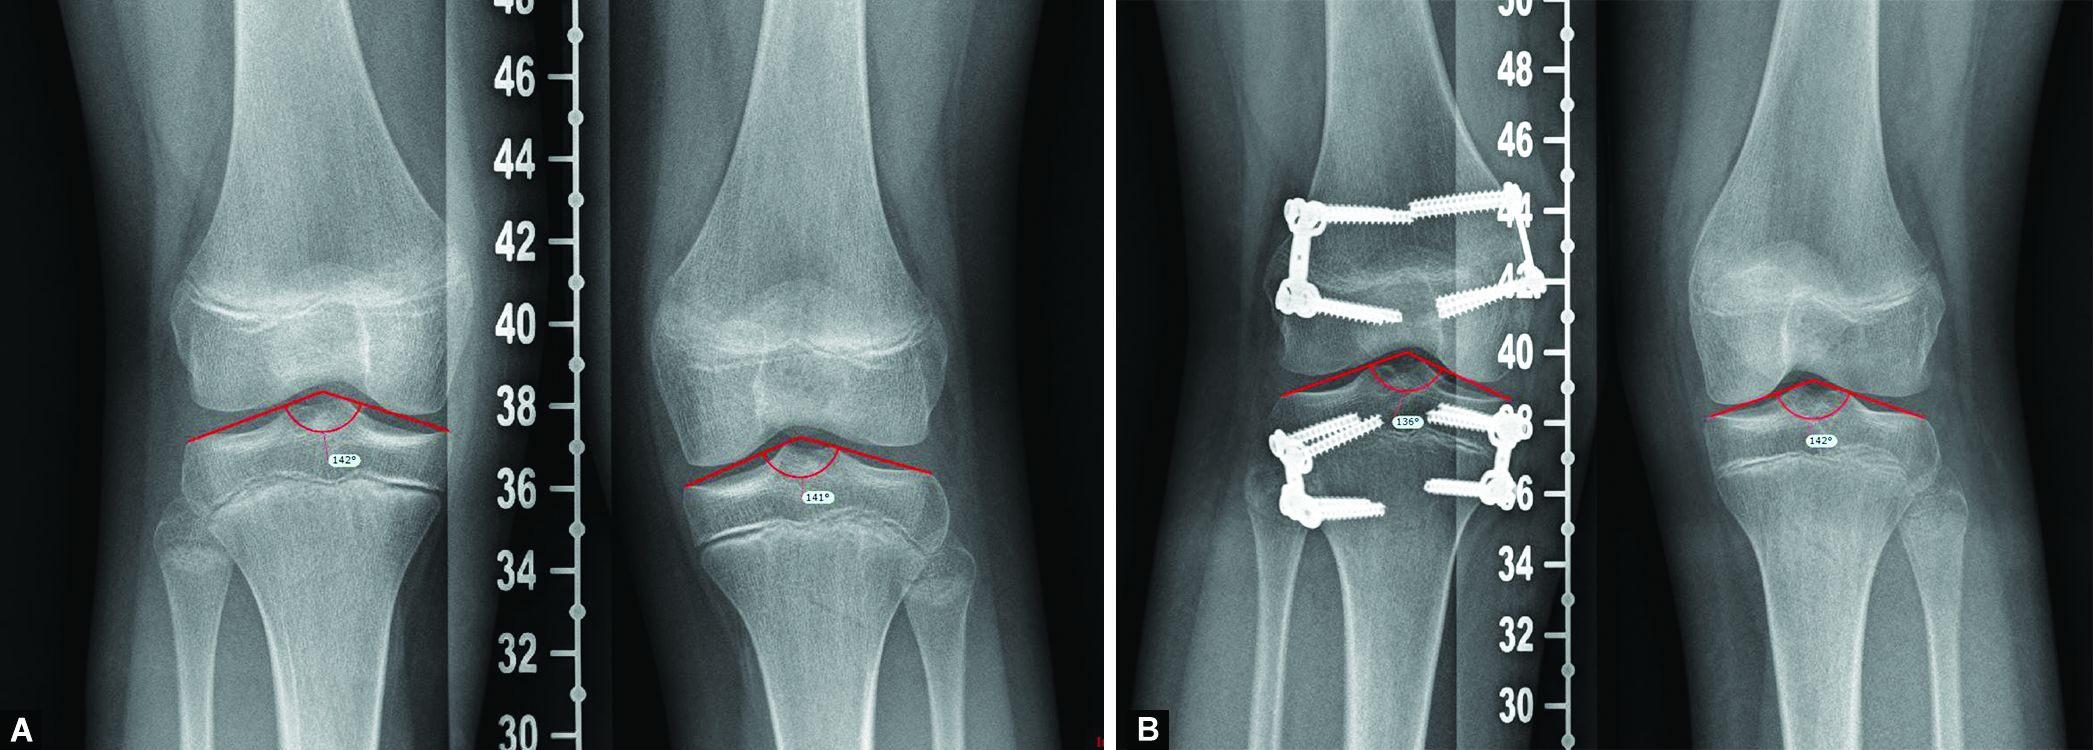

From www.researchgate.net

Measurements were performed on longstanding Xrays. a Limb length Leg Length Discrepancy Surgery Growth Plate The growth plate fusion procedure. Leg length discrepancy is a common condition that may be caused by a congenital defect, disruption of the physis, or a paralytic disorder and presents with limb length. The limb length discrepancy will gradually lessen as the opposite leg continues to grow and catch up. The surgeon may place metal staples, or a. This will. Leg Length Discrepancy Surgery Growth Plate.

(PDF) Guided growth with tension band plate or definitive Leg Length Discrepancy Surgery Growth Plate The growth plate fusion procedure. Leg length discrepancy is a common condition that may be caused by a congenital defect, disruption of the physis, or a paralytic disorder and presents with limb length. This procedure slows the growth of the opposite leg or arm by altering the activity of the growth plate, thereby allowing the affected limb to “catch up”. Leg Length Discrepancy Surgery Growth Plate.